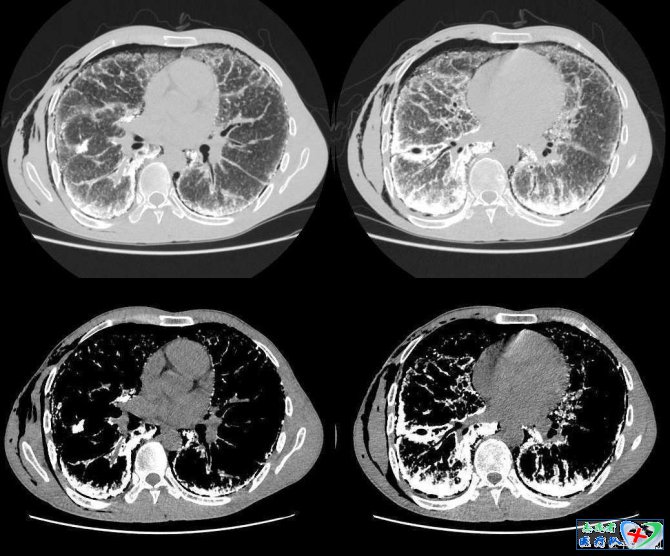

10、横S征(反S征):

当肿瘤发生于右上叶支气管时,X线可见右肺门肿块与右上叶不张相连,构成形似S横着写的征象,为右上叶中央型肺癌特征性表现。因为右肺上叶位于斜裂前方,下方以水平裂为界,侧方位胸壁,内测是纵隔。当右肺上叶容积缩小,根据容积缩小的程度出现的解剖改变包括胸膜裂移位、结构变化及肺密度增加。在右肺上叶不张时水平裂和斜裂向纵隔方向向上、内移动,右肺中、下叶代偿性膨胀,后前位胸部X线片上可见水平裂向下凹,形成代表肺叶不张三角形密度影,尖端指向肺门,外缘以胸壁为宽基,严重的右上肺不张可以与纵隔平行,和纵隔宽相似,或向上压缩如尖帽。此时,如果有一个较大的肺门肿块出现,与凹面向下的水平裂结合,在后前位胸部平片上就形成横S征。其实,不只是在右肺上叶,只要肿瘤或淋巴结压迫上叶支气管导致肺不张,就会由肿块和不张肺边缘形成此种征象。其次,横S征也不是只在X线上看到,在CT上同样可以见到。上一篇:浅谈女性的生理周期 下一篇:膝关节疼痛的诊断与鉴别诊断